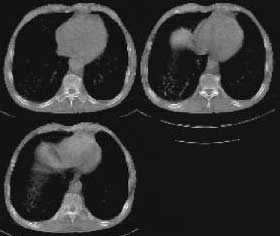

以下是引用woaixct在2006-6-23 12:15:00的发言:[br]第一张胸片示:右肺上叶为大片致密影占据,左肺上见大片致影及空洞性病灶并有液平;[br]第二张胸片示:左肺上叶致密影及空洞性病灶基本吸收,而右肺上叶之病灶有少许吸收改变;[br]ct片示:右上叶大片软组织密度,右肺门区至右肺上叶见巨大软组织块,内见支气管充气征,上纵隔右移,主气管及上叶支气受压变扁,中间支气管狭窄,左肺上叶空洞性病灶并有液平,左肺上叶尖后段见大片致密影,结合2张胸片考虑,ct片是4月份所摄,而不是6月份的片子;[br]结合2张胸片及ct片考虑:[br] 1.右中央型肺癌伴右肺上叶不张;[br] 2.左肺上叶尖后段炎性变及左肺脓肿;[br]第2张胸片提示:经过一个多月的不规则抗炎治疗,左肺上叶病灶及右肺上叶不张病灶基本吸收,而右肺占位无明显变化。

以下是引用jiangjing在2006-6-23 21:21:00的发言:[br]个人考虑还是两肺感染性病变可能大,主支气管及叶支气管是通畅的,并可见支气管气相;ct提示病变是以肺叶分布的,密度相对均匀;胸片可见有叶间裂下坠征,是不是考虑克雷伯杆菌感染可能.病人前后两张片比较病变是增多[应该考虑混合感染可能性大,右肺癌待排建议查痰及穿刺检查]